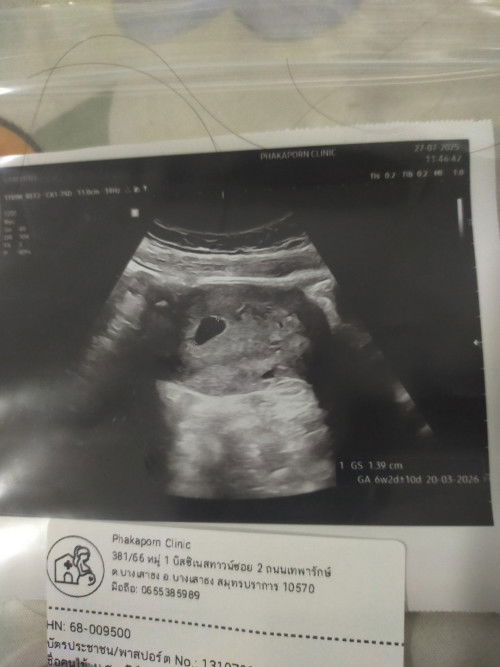

ท้อง6วีค อัลตราซาวแล้วยังไม่เจอน้อง

ท้อง7วีค อัลตร้าซาวด์เจอแต่ถุงไข่ไม่เจอน้องเลย แอบกังวล คุณหมอบอกอีกอีก2ทิตไปใหม่

6 วีคยังไม่เห็นตัวน้องก็ปกติค่ะ